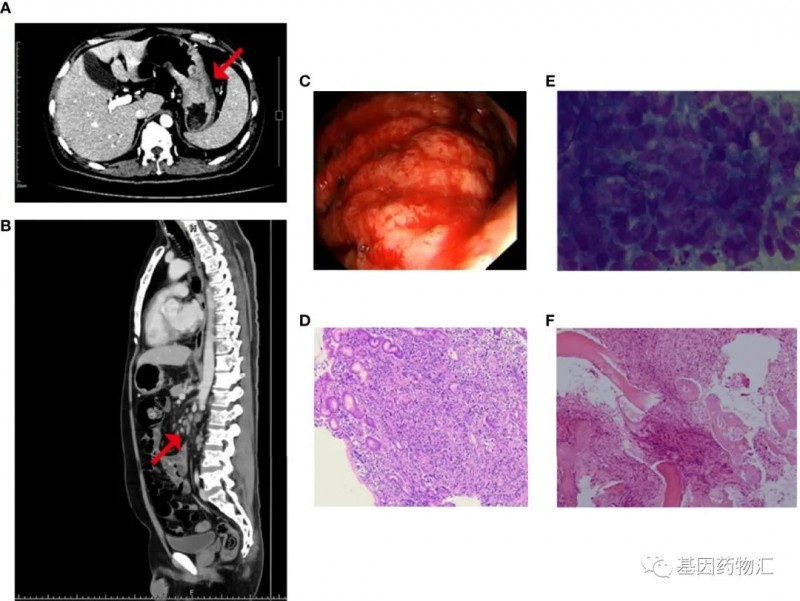

另一位47岁的胃癌患者,基本状态较差:无法行走、血小板严重降低(14×10^9/L)。CT显示患者胃底及胃体增厚,胃周、肝门、腹膜后、纵隔及双侧肺门区多处淋巴结转移,且存在广泛的全身性骨转移(右侧额骨眶上缘、双侧锁骨、双侧肩胛骨、多根肋骨、胸椎、腰椎和骶椎、骨盆骨、右侧肱骨和双侧股骨上部)。

二代测序结果提示患者存在MET扩增及MET ST7重排,微卫星稳定,肿瘤突变负荷中等(6.3个突变/Mb),分期为ⅣB期。

至入院21天,患者开始出现发热、肺部感染、急性左心衰竭,病情危笃!结合患者的情况,医生最终为他选择了赛沃替尼(沃利替尼,savolitinib)方案。

令人欣喜的是,塞沃替尼方案的效果非常显著!治疗4天后,患者血小板恢复至27×10^9/L,骨痛等症状也明显开始缓解;治疗18天,患者血小板恢复至81×10^9/L,达到了出院的标准。

至治疗55天回访时,患者的血小板(188×10^9/L)、血红蛋白(111g/L)以及白细胞都恢复到了正常水平,肿瘤标志物也明显降低,CT复查胃底和体壁变薄,淋巴结缩小,骨髓图片显示无转移性癌细胞。根据标准,患者已经达到了部分缓解。